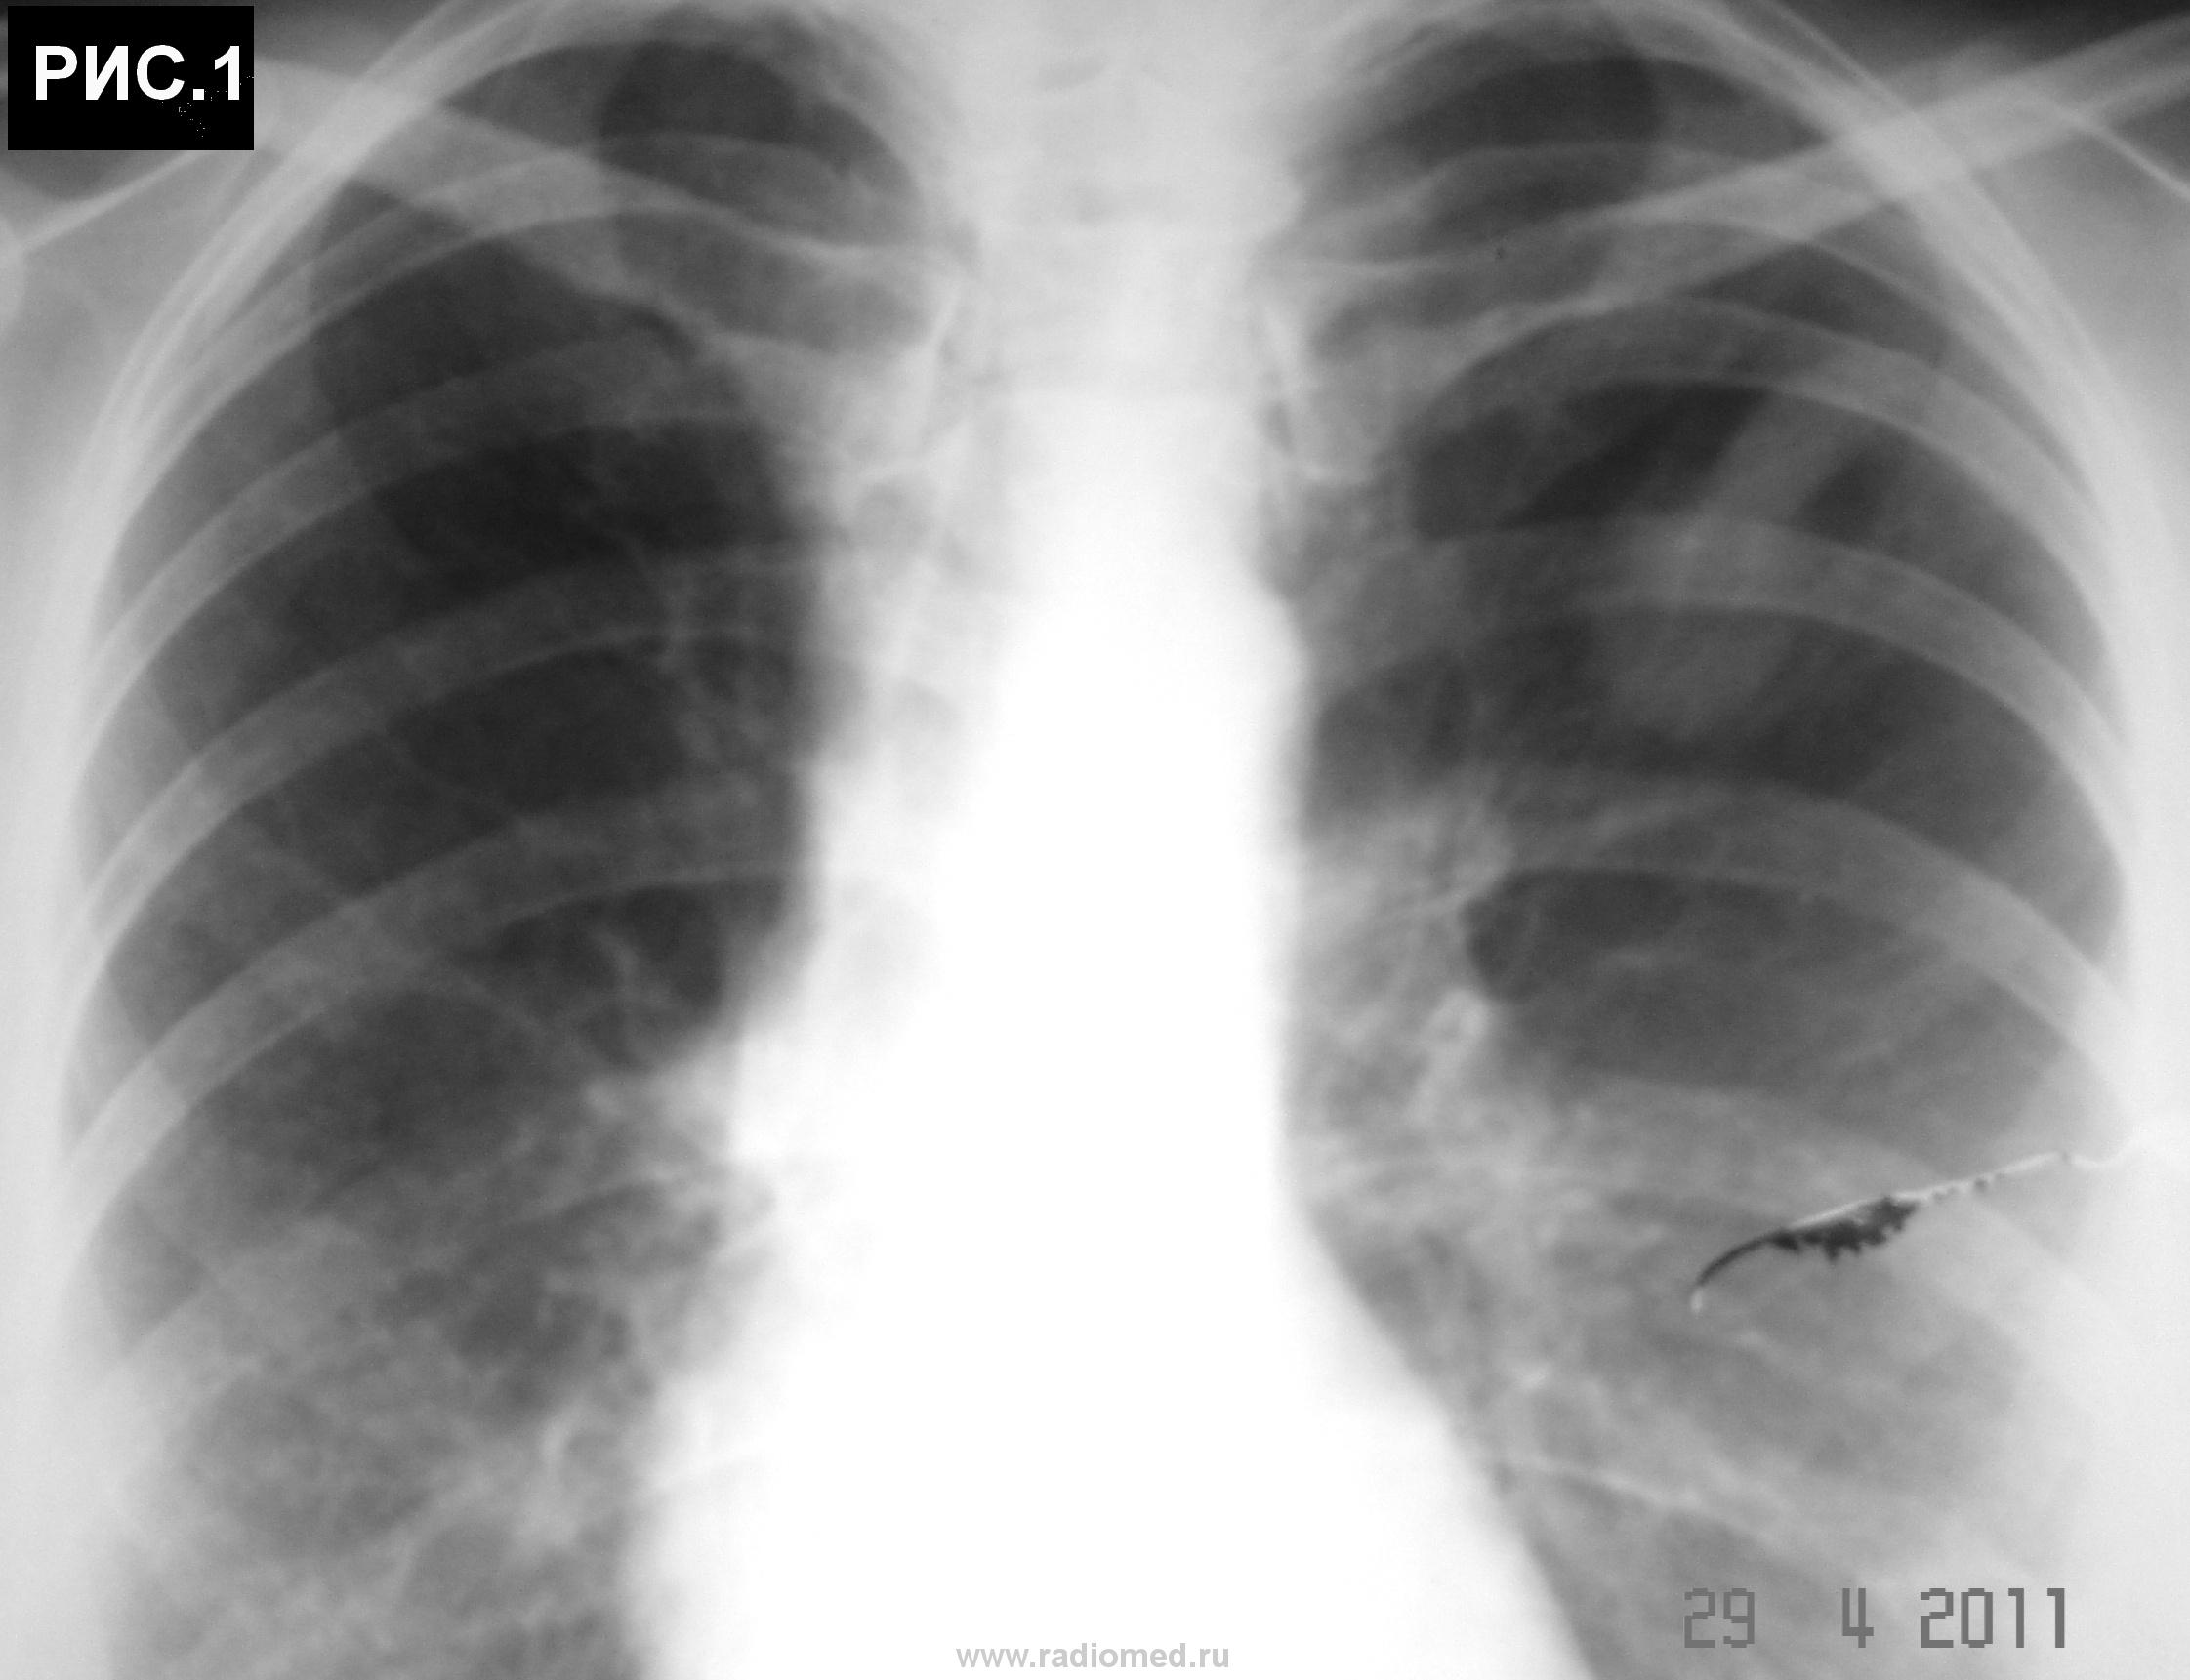

Б-ная 54 г. Живет в небольшом  городе. Поступила в хирургический стационар для холецистэктомии. При ней находился пакет с рентгенограммами органов грудной клетки. Стало известно, что 1 год назад обратилась с бронхолегочными симптомами в поликлинику, где при рентгенографии грудной клетки "выявлено затемнение в легких". После лечения антибиотиками изменения в легких оставались стабильными. Консультирована рентгенологами,онкологами, фтизиатрами, терапевтами, хирургами. Диагноз не установлен. Больная удручена.Хирурги думают. Снимки 6 мес. давности (рис.1,2,3 ).  Рентгенограммы не блеск, но картина везде подобная. Томограмм нет. Ваше слово коллеги! С уважением Nic.

наступил, когда был выполнен последний снимок в отделении. Хорошо видно, что имеется частичное опорожнение ретенционной бронхиальной кисты (рис.4, рис.5). Со слов больной,  незадолго до поступления в стационар имело место отхождение мокроты светлокоричневого цвета без запаха. При анализе выписок из различных учреждений процесс в легких рассматривался как туберкулема легких, туберкулема легких или опухоль, опухоль легкого, патология сосудов легкого, диагноз неясен (овальный фокус затемнения в легком). С уважением Nikolas